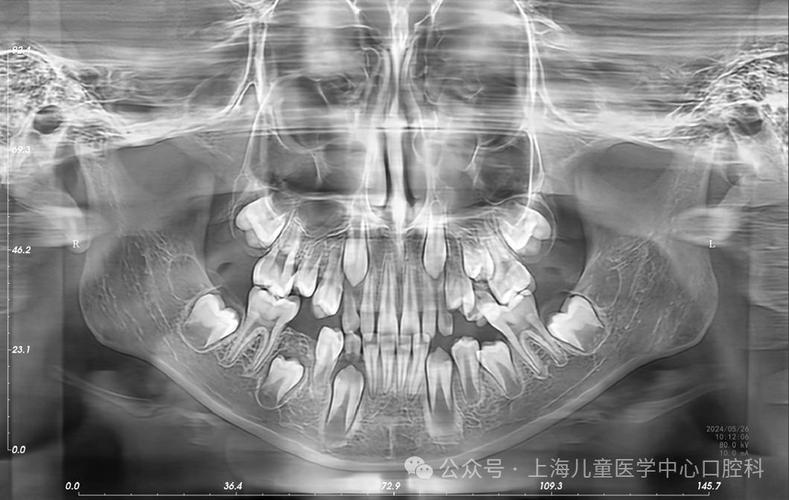

- 权衡利弊:牙医开具全景片检查,是为了获得诊断疾病和制定治疗计划所必需的全面信息,其带来的诊断价值远远大于其微乎其微的辐射风险,没有这些影像,可能会漏掉重要的疾病(如埋伏牙、囊肿、肿瘤、严重的牙槽骨吸收等),导致更严重的后果。

- 儿童:儿童对辐射比成人更敏感,但儿童在正畸、拔除多生牙等治疗中,全景片又是必不可少的,牙科医生会遵循“ALARA”(As Low As Reasonably Achievable,合理可行尽量低)原则,使用儿童专属的更低剂量参数,并严格遮盖甲状腺等敏感部位。